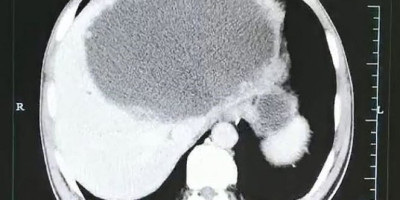

Naime, na rendgenskom snimku videli su da se u jetri Kineza nalazi ogroman broj malih jajašca koje su tamo polozili parazitski crvi.

I sami lekari bili su šokirani kada su videli gnojnu masu sa jajašcima, koja je bila duga 19 centimetara, široka 18, a duboka 12, i bila je smeštena na levom režnju jetre.

Prvo su pokušali da je uklone isisavajući tečnost, ali to nije pomoglo, pa su čoveku uklonili pola jetre.

Kako su saopštili, veruju da je parazit ušao u čovekovo telo preko žive ribe, za koju je sam priznao da je jeo, prenosi Dejli mejl.